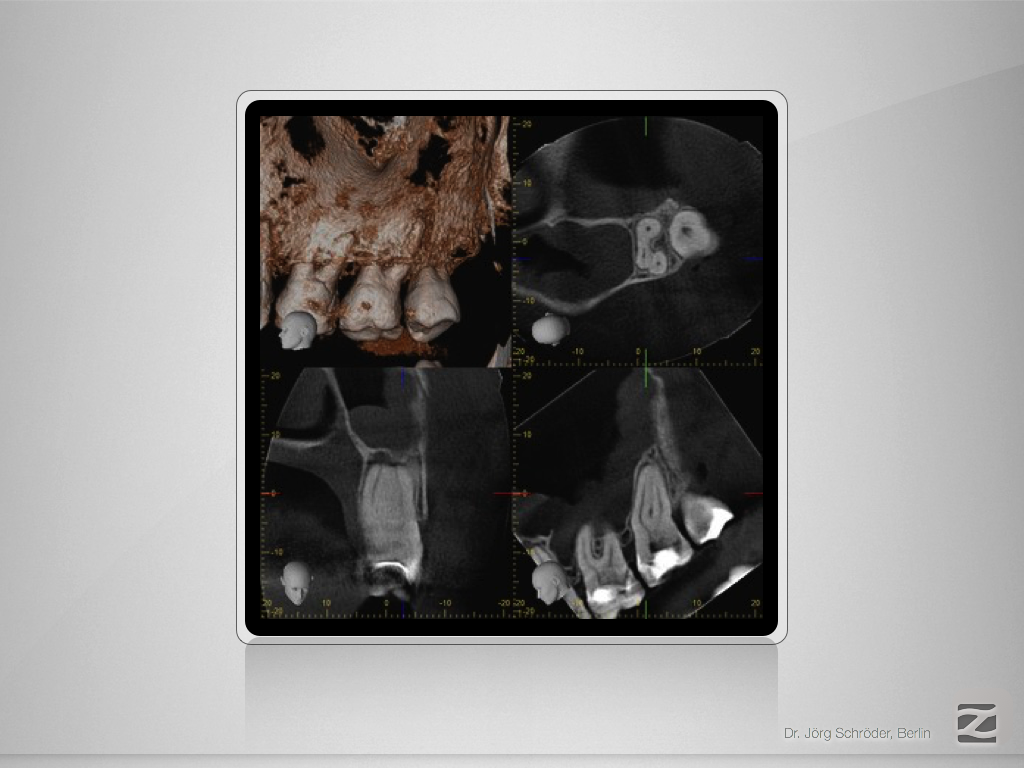

27D.003

Mutter aller Dentikel